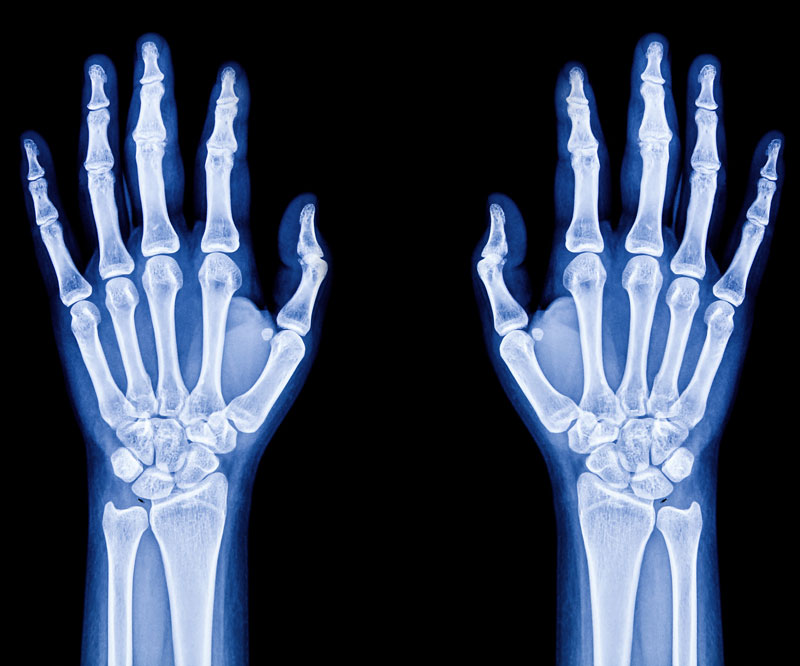

Made up of 26 bones connected by many joints, muscles, tendons and ligaments, the foot is one of the most complex parts of the body.